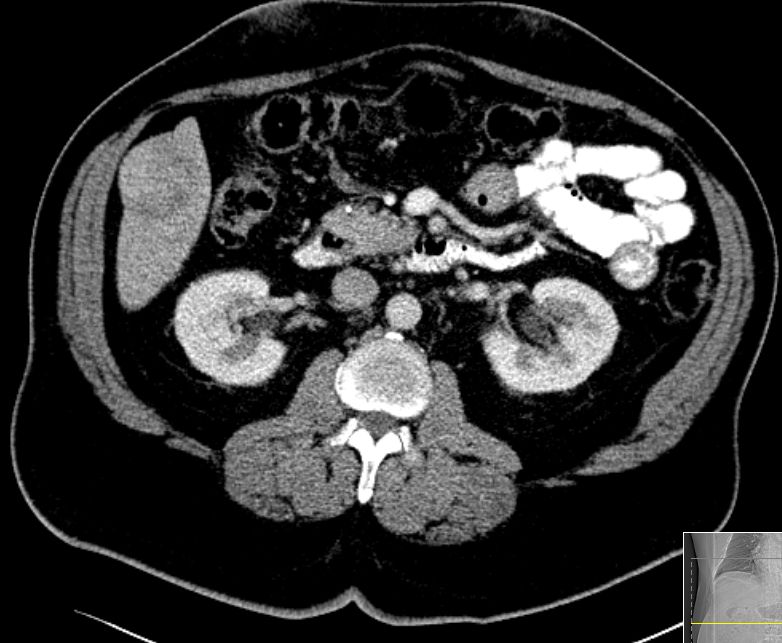

| CT | 60-jähriger Mann mit hepatozellulärem Karzinom in Segment 6.

Histologie: mäßig differenziertes hepatozelluläres Karzinom, G2, Stadium pT1![]() |